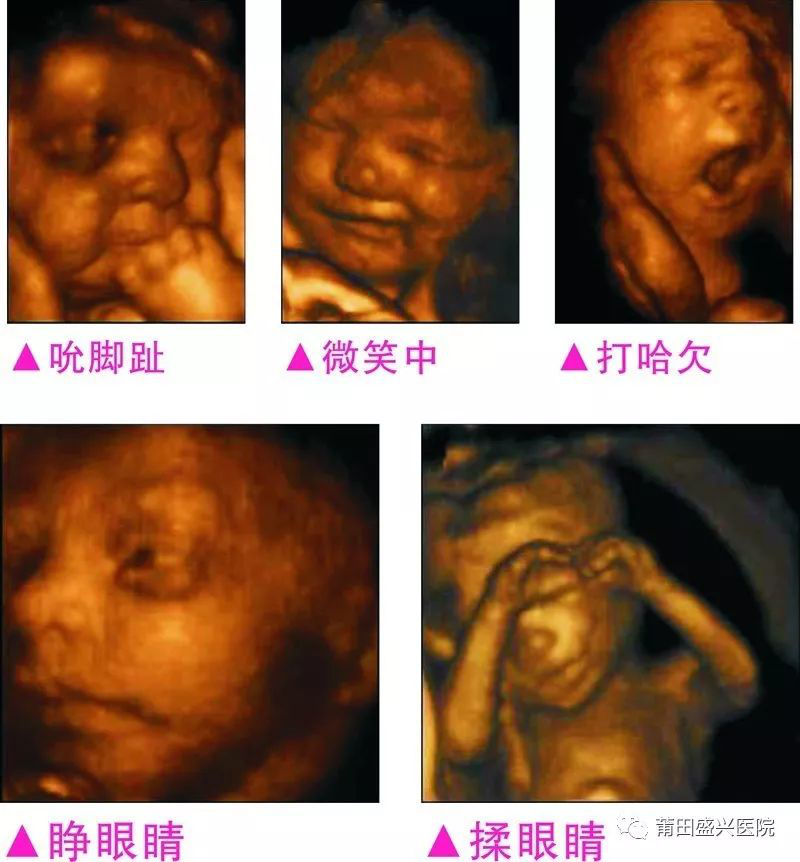

您一定不知道寶寶有多調(diào)皮可愛(ài)

你一定不知道寶寶這么小就有這么多表情

3完整記錄胎兒高清動(dòng)態(tài)寫(xiě)真

四維容積成像技術(shù),智能光源系統(tǒng)展現(xiàn)梯度亮度,渲染畫(huà)面,提高容積成像品質(zhì),高清顯示腹中寶寶的實(shí)時(shí)動(dòng)態(tài)影像,完整記錄寶寶的一舉一動(dòng),讓準(zhǔn)爸媽與寶寶Di一次幸福“見(jiàn)面”,更可刻錄成高清視頻,送給未來(lái)寶寶的珍貴禮物。